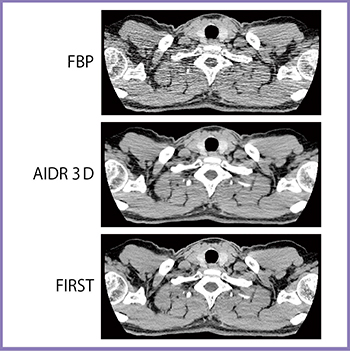

空間分解能については,櫛状ファントムによる検討から,FBP,AIDR 3Dと比べてFIRSTは高い分解能を有していることがわかる(図1)。空間分解能が向上することでパーシャルボリューム効果の影響が軽減し,CT値の精度も向上すると考えられる。また,FIRSTでは統計学的ノイズモデルを用いており,重み付けによる再構成データの選択によりノイズの多いデータを除外することで,ストリークアーチファクトの大幅な低減が可能になった(図2)。さらに,FIRSTでは再構成関数を用いないため,高吸収体周囲のアンダーシュートが原理的に発生しない。

図2 ストリークアーチファクトの減少